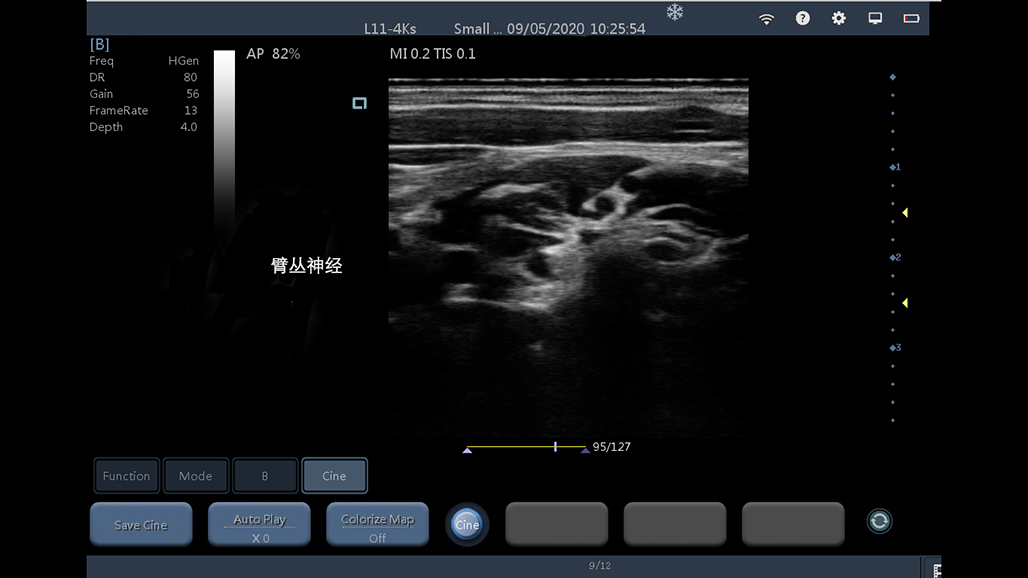

• 线阵

神经

肌骨等